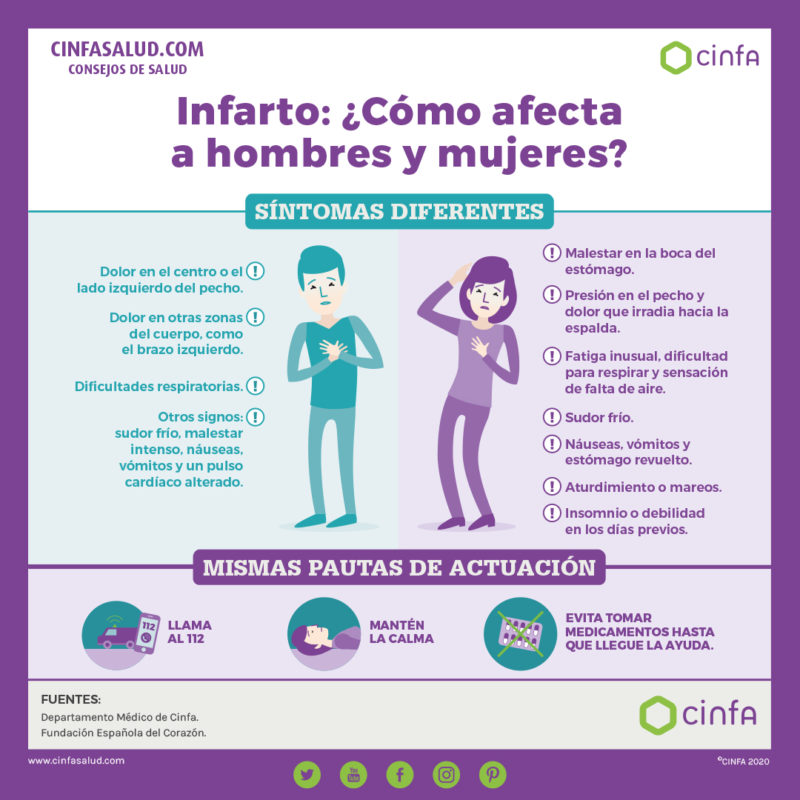

En los varones, el dolor en el centro del pecho o en el lado izquierdo del tórax, que a veces irradia hacia el brazo izquierdo o la mandíbula, es uno de los signos de alarma más comunes. Este dolor no se modifica con los movimientos o respiración y dura más de 20 minutos. También pueden darse dificultades respiratorias, sudor frío, malestar intenso, náuseas, vómitos y pulso cardíaco alterado.

“En cambio, un infarto en las mujeres puede manifestarse con malestar en la boca del estómago y presión en el pecho o dolor que irradia hacia la espalda. Igualmente, el dolor no cede con los movimientos, ni con la respiración. También puede experimentarse sudor frío, dificultad para respirar, náuseas, vómitos y estómago revuelto. Es importante saber todo esto y no considerar el dolor en el pecho como único indicativo de infarto para poder identificarlo cuando ocurre”, recalca el experto de Cinfa.

En caso de que alguien esté sufriendo un infarto de miocardio a nuestro alrededor, lo primordial es contactar con los servicios de Emergencias y llamar inmediatamente al 112. De esta manera, los profesionales sanitarios podrán aconsejar a los acompañantes y al paciente y trasladarlo rápidamente al hospital para iniciar el tratamiento oportuno.

“Hasta que lleguen los sanitarios, deberemos seguir las indicaciones que nos den en el 112. Se ha comentado mucho la conveniencia o no de administrar aspirina–apunta el doctor Maset-, pero dado que, en ocasiones, puede haber contraindicación, lo mejor es seguir las recomendaciones que nos den los sanitarios”.

También es muy importante mantener y transmitir calma dentro de lo posible, ya que el estrés y la ansiedad afectan al corazón, lo que aumenta la frecuencia cardíaca y la tensión arterial.